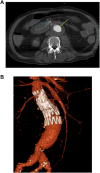

Secondary aorto-enteric fistulas (AEFs) are an uncommon but serious complication of abdominal aortic aneurysm (AAA) repair. Case review of two cases of secondary AEF are as follows: the first case involved a 75-year- old male who presented with AEF 1 year post-emergency open AAA repair, successfully managed with endovascular aortic aneurysm repair (EVAR) without complication. The second case involved a 75-year-old male patient 14 months post open AAA repair for an inflammatory aneurysm who presented with an iliac-enteric fistula. The previous repair was relined with a bifurcated EVAR with subsequent laparotomy and resection of the affected portion of the small bowel. Both patients on lifelong antibiotics without further episodes of sepsis, recurrence of AEF or mortality at 12 months follow up. EVAR can be successful in the management of secondary AEF. Careful patient selection, accurate image interpretation, and expedient management are key factors to successful short- and long-term outcomes.